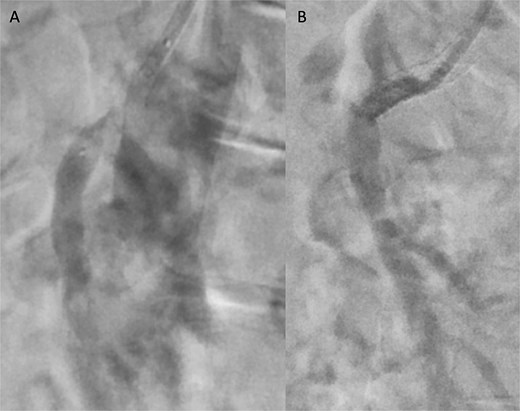

A 76-year-old female patient with a medical history of diabetes mellitus and cholecystectomy presented to the emergency department with a 7-month history of postprandial abdominal pain, food fear, and weight loss (25–30 kg). Over the past 3 days she referred symptom worsening to constant pain. On the physical examination, the abdomen was tender to palpation. Laboratory results revealed leukocytosis (13.700/μl), high C-reactive protein (23 mg/dl) and lactate 0.7 mmol/L. A previously performed computed tomography angiography (CTA) in context of a lithiasic cholecystitis revealed celiac trunk occlusion and pre-occlusive stenosis of the SMA ostium but the patient was not referred for a vascular surgery consultation. A CTA scan obtained in the emergency department revealed thrombotic occlusion of the SMA origin associated with distal embolization (Fig. 1A–C). In this context, the diagnosis of acute-on-chronic mesenteric ischemia was assumed, and the patient was proposed for urgent endovascular revascularization. A 7F (French) sheath was placed via percutaneous access in the left brachial artery, and SMA catheterization was performed using a triaxial system (sheath, MP catheter and Progreat® catheter). Diagnostic angiography confirmed the CT findings (Fig. 2A). Catheter-directed thrombolysis was first performed with a 5 ml bolus of alteplase, followed by percutaneous thrombectomy using the Penumbra® system (Fig. 2B), with retrieval of fresh thrombus (Fig. 3). Primary stenting of the SMA ostium was also performed using an Advanta® 6 × 39 mm stent with proximal flair, with an excellent imagological result (Fig. 4A and B). The postoperative course was uneventful, with significant improvement of symptoms and clinical status. A CTA prior to discharge revealed a patent stent with proper placement and no evidence of residual thrombus (Fig. 5A and B). The patient was discharged on the seventh postoperative day with apixaban 5 mg twice daily. Follow-up of the patient at 6 months revealed that the stent remained patent, with no reported abdominal complaints. The patient gained 15 kg at this point of follow-up.

Pre-discharge follow-up CTA showing patent SMA and no complications, with coronal (A) and sagittal (B) images.